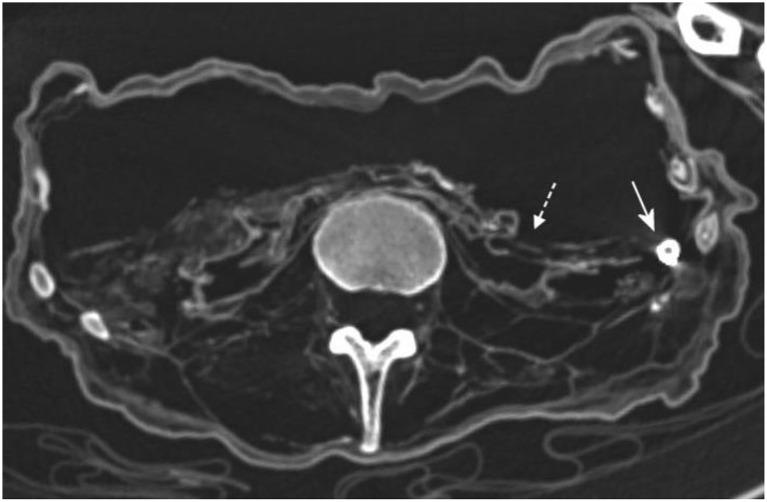

The multidisciplinary study of the well preserved cadaver of the so-called "air-dried chaplain" from the church crypt of St. Thomas am Blasenstein (Upper Austria) not only solved the "mystery" of the excellent preservation of the trunk of this unusual mummified human body, but also provided circumstantial information about this historic individual, his life and disease history, and conclusion of his cause of death. The mummy of a 35-45 year old male, radiocarbon dated to the period 1730-1780 CE is most likely that of the local aristocratic parish vicar Franz Xaver Sidler von Rosenegg who had been temporarily delegated to St. Thomas parish from his mother monastery of Waldhausen im Strudengau (Upper Austria). He had a high-quality diet based on terrestrial animal products, showed no signs of major physical work load, was most likely a pipe smoker and suffered from chronic active pulmonary tuberculosis with peripheral and central (hilar) calcifications (primary tuberculous complex) and a right lower lobe cavity with focal heterotopic ossification and potential active inflammation. This latter may have caused acute pulmonary hemorrhage which may have been the cause of death. Most surprisingly, we detected, in the otherwise completely intact abdominal (and pelvic) cavity, extensive packing with foreign material which was identified as a mixture of wood chips, fragmented twigs, large amounts of fabric of various types including elaborate embroidered linen, and even pieces of silk. Furthermore, this embalming method seems to have included high level zinc-ion solution impregnation (most likely zinc-chloride with small amounts of arsenic) and the addition of copper. The packing was inserted into the abdominal body cavity through the rectum. It led to an excellent state of conservation of the trunk, while the face (and skull) and peripheral extremities were less well preserved.

对来自奥地利上奥地利州布拉森施泰因的圣托马斯教堂地下室所谓“风干牧师”保存完好的尸体进行的多学科研究,不仅解开了这具不同寻常的木乃伊化人体躯干保存完好的“谜团”,还提供了有关这位历史人物、他的生活和病史以及死因推断的间接信息。这具35至45岁男性的木乃伊,经放射性碳测定年代为公元1730年至1780年,很可能是当地贵族教区牧师弗朗茨·克萨韦尔·西德勒·冯·罗森艾格的,他曾从其位于奥地利上奥地利州施特鲁登高的瓦尔hausen母亲修道院临时被委派到圣托马斯教区。他以陆地动物产品为基础的饮食质量很高,没有显示出主要体力劳动负担的迹象,很可能是个吸烟者,患有慢性活动性肺结核,伴有外周和中央(肺门)钙化(原发性结核复合体)以及右下叶空洞,伴有局灶性异位骨化和潜在的活动性炎症。后者可能导致了急性肺出血,这可能是死因。最令人惊讶的是,在原本完全完整的腹腔(和盆腔)中,我们发现有大量异物填充,这些异物被鉴定为木屑、碎树枝、各种类型的大量织物(包括精致的绣花亚麻布)甚至丝绸碎片的混合物。此外,这种防腐方法似乎包括高浓度锌离子溶液浸渍(很可能是氯化锌加少量砷)以及添加铜。填充物通过直肠插入腹腔。这使得躯干保存得非常完好,而面部(和头骨)以及四肢保存得较差。